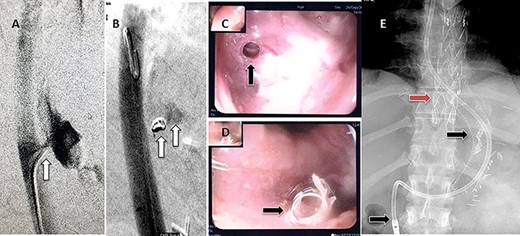

A 36-year-old male, involved in a minor motor vehicle accident while driving his car. He lost consciousness following a sudden onset of transient loss of vision which was not associated with palpitation or dizziness. His previous medical history revealed arterial hypertension and a corrected aortic coarctation with interposition graft at the age of 14. Pan CT scan was unremarkable except for thickening of the desending throacic aorta. His white blood count was very high (68 000 per cubic millimeter of blood). One day after the car accident, he developed nausea, hematemesis and melana. Upper GI endoscopy revealed blood in the stomach and distal esophafgus with no identifiable source of bleeding (Fig. 6). The patient developed massive hematemsis with hypotension requiring intubation and resuscitation. Another CT scan showed air pocket around distal aorta and contrast extravasation to the esophagus (Fig. 7). Another endoscopy revealed distal esophageal ulcer with clot extending toward the stomach (Fig. 8). AEF was suspected and then confirmed by aortogram. The fistula was treated by TEVAR (20 mm × 11.5 cm Valiant covered stent - Medtronic company, USA) followed by fully covered esophageal stent in the middle of the esophagus (Fig. 9).

First upper endoscopy blood within the stomach and duodenum; the esophagus image was not clear and no active bleed can be seen.

(A) CT study with contrast showing gas adjacent to the descending thoracic aorta with thickened soft tissue around the esophagus. (B) Vascular contrast within the esophagus and projecting outside the aorta forming ‘pseudoaneurysm’ or penetrating aortic ulcer.

Second upper endoscopy fresh bleeding from the distal esophagus and after washing the blood an adherent clot extending from an ulcer going down into the stomach can be seen.